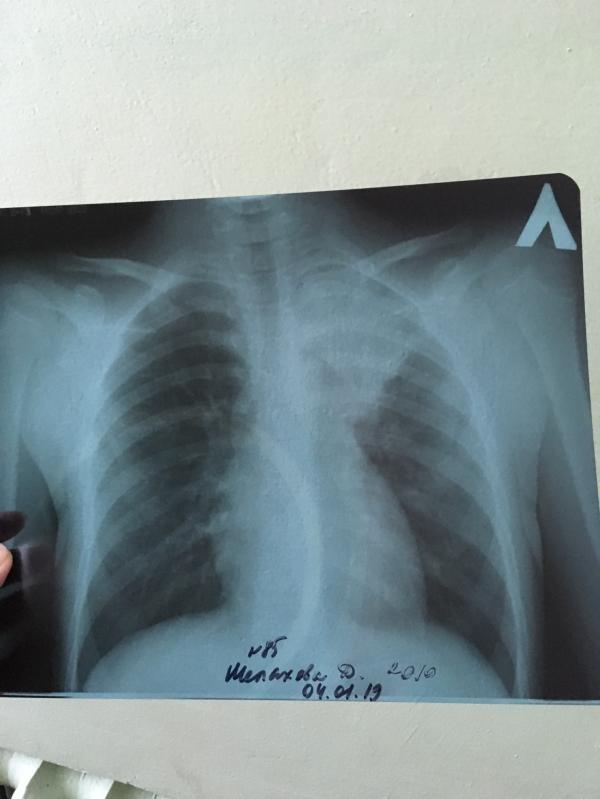

‼️☝🏻Хочу просто предупредить как сейчас бывает!! Заболела дочь☝🏻Сначала поднялась просто температура к вечеру после новогодней ёлки 38,5! Утром 39,2!! Дали жаропонижающее. Спала до 37,5 и так три дня. Больше никаких симптомов. С виду обычный ребёнок. Затем появился кашель, но не сильный. Слегка подкашливала. Скорую вызывали, к врачу ходили: диагноз ОРВИ. Хрипов нет в лёгких. А температура всё продолжала подниматься высокая, и даже когда стали пить антибиотик была 38,5☝🏻Поехали в больницу, сдали анализы: отличные! Ребёнок на вид здоров, ни соплей, ни горло, кашель редкий, анализы в норме🤷♀️врач думает🤔от чего может держаться температура 8 дней выше 38,5 даже после приема антибиотика??! Я настояла на рентгене ( врач отказывается делать, типо не может быть, у вас бы были симптомы(насморк, кашель сильный, головокружение, слабость и тд...)). В итоге после моих уговоров сделали рентген и оказалось 😱левосторонняя плевропневмония‼️☝🏻вот тебе и НАти!! Так что имейте ввиду как бывает! Сейчас ходит вирусная пневмония 😷 остерегайтесь и будьте все здоровы🙏в новом году👋🤗

Вот в том то и дело, что у всех по разному. Просто у нас девочка одноклассница заболела пневмонией и у неё всё по другому было! У неё не было температуры! Только насморк и кашель! Кашель дикий! И врач сразу услышала хрипы и отправила на рентген. И у неё на снимке были только кончики затемнённые! Легкая форма называется! А у нас сложная как оказалось. Поэтому я предупредила и вдруг у кого-то было по другому, может напишут, как, чтобы знать как может быть! Вот в чем дело 😟